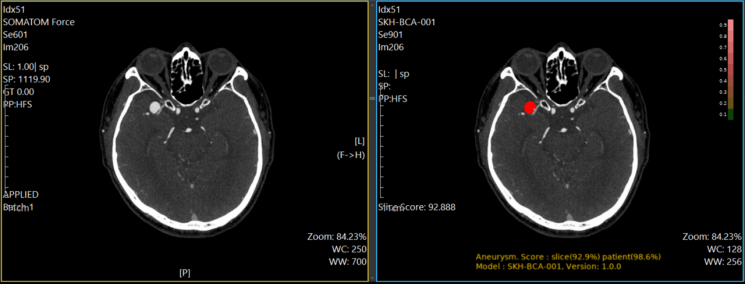

PurpleAI's cerebral aneurysm diagnostic AI solution automatically detects suspected aneurysm areas in patients' vascular CT images, helping medical professionals make faster and more accurate diagnoses. Clinical trials conducted at Seoul National University Hospital and Ajou University Hospital demonstrated that the solution improved physicians' diagnostic sensitivity for cerebral aneurysms by more than 10 percentage points. Notably, for small aneurysms less than 3mm, the AI's diagnostic sensitivity was about 18 percentage points higher than that of physicians.

This solution is the first CT image-based AI medical device for cerebral aneurysm diagnosis in Korea. Cerebral aneurysms are examined using CTA (CT angiography) or MRA (magnetic resonance angiography). Compared to MRA, CTA offers much shorter examination times and lower costs, making it widely used in clinical practice. While some CT image-based AI solutions with FDA approval exist in the global market, all of them only detect aneurysms 4mm or larger, giving PurpleAI's solution a performance advantage.